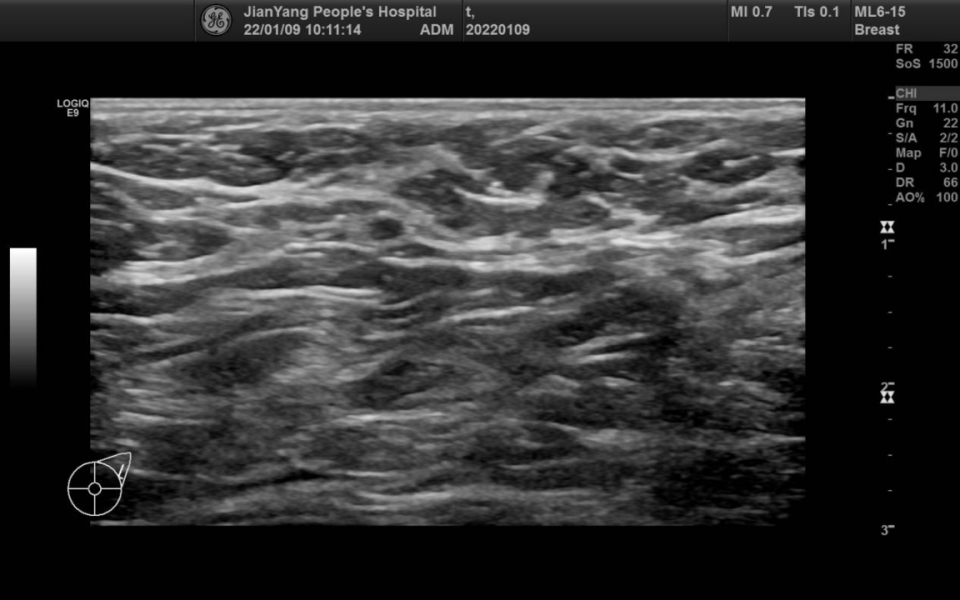

申请超声检查图像如下:

图片图 1 左乳 2 点钟方向肿物

图片图 2 左乳 2 点钟方向肿物

图片图 3 左乳 2 点钟方向肿物

两侧乳房切面形态轮廓正常,层次清楚,腺体回声不均匀,左乳 2 点钟方向距乳头约 20 mm 处可见范围约 28.3 mm x 22.4 mm x 28.1 mm 的低回声团,略呈分叶状,边界清楚,内可见不规则无回声区,其内可见较多条状血流信号。

双乳导管未见明显扩张征像。CDFI:余腺体内未见异常血流信号。

双侧腋窝及双侧锁骨上下区未见明显长大淋巴结声像。

超声提示:左乳低回声团 BI-RADS 4A 类